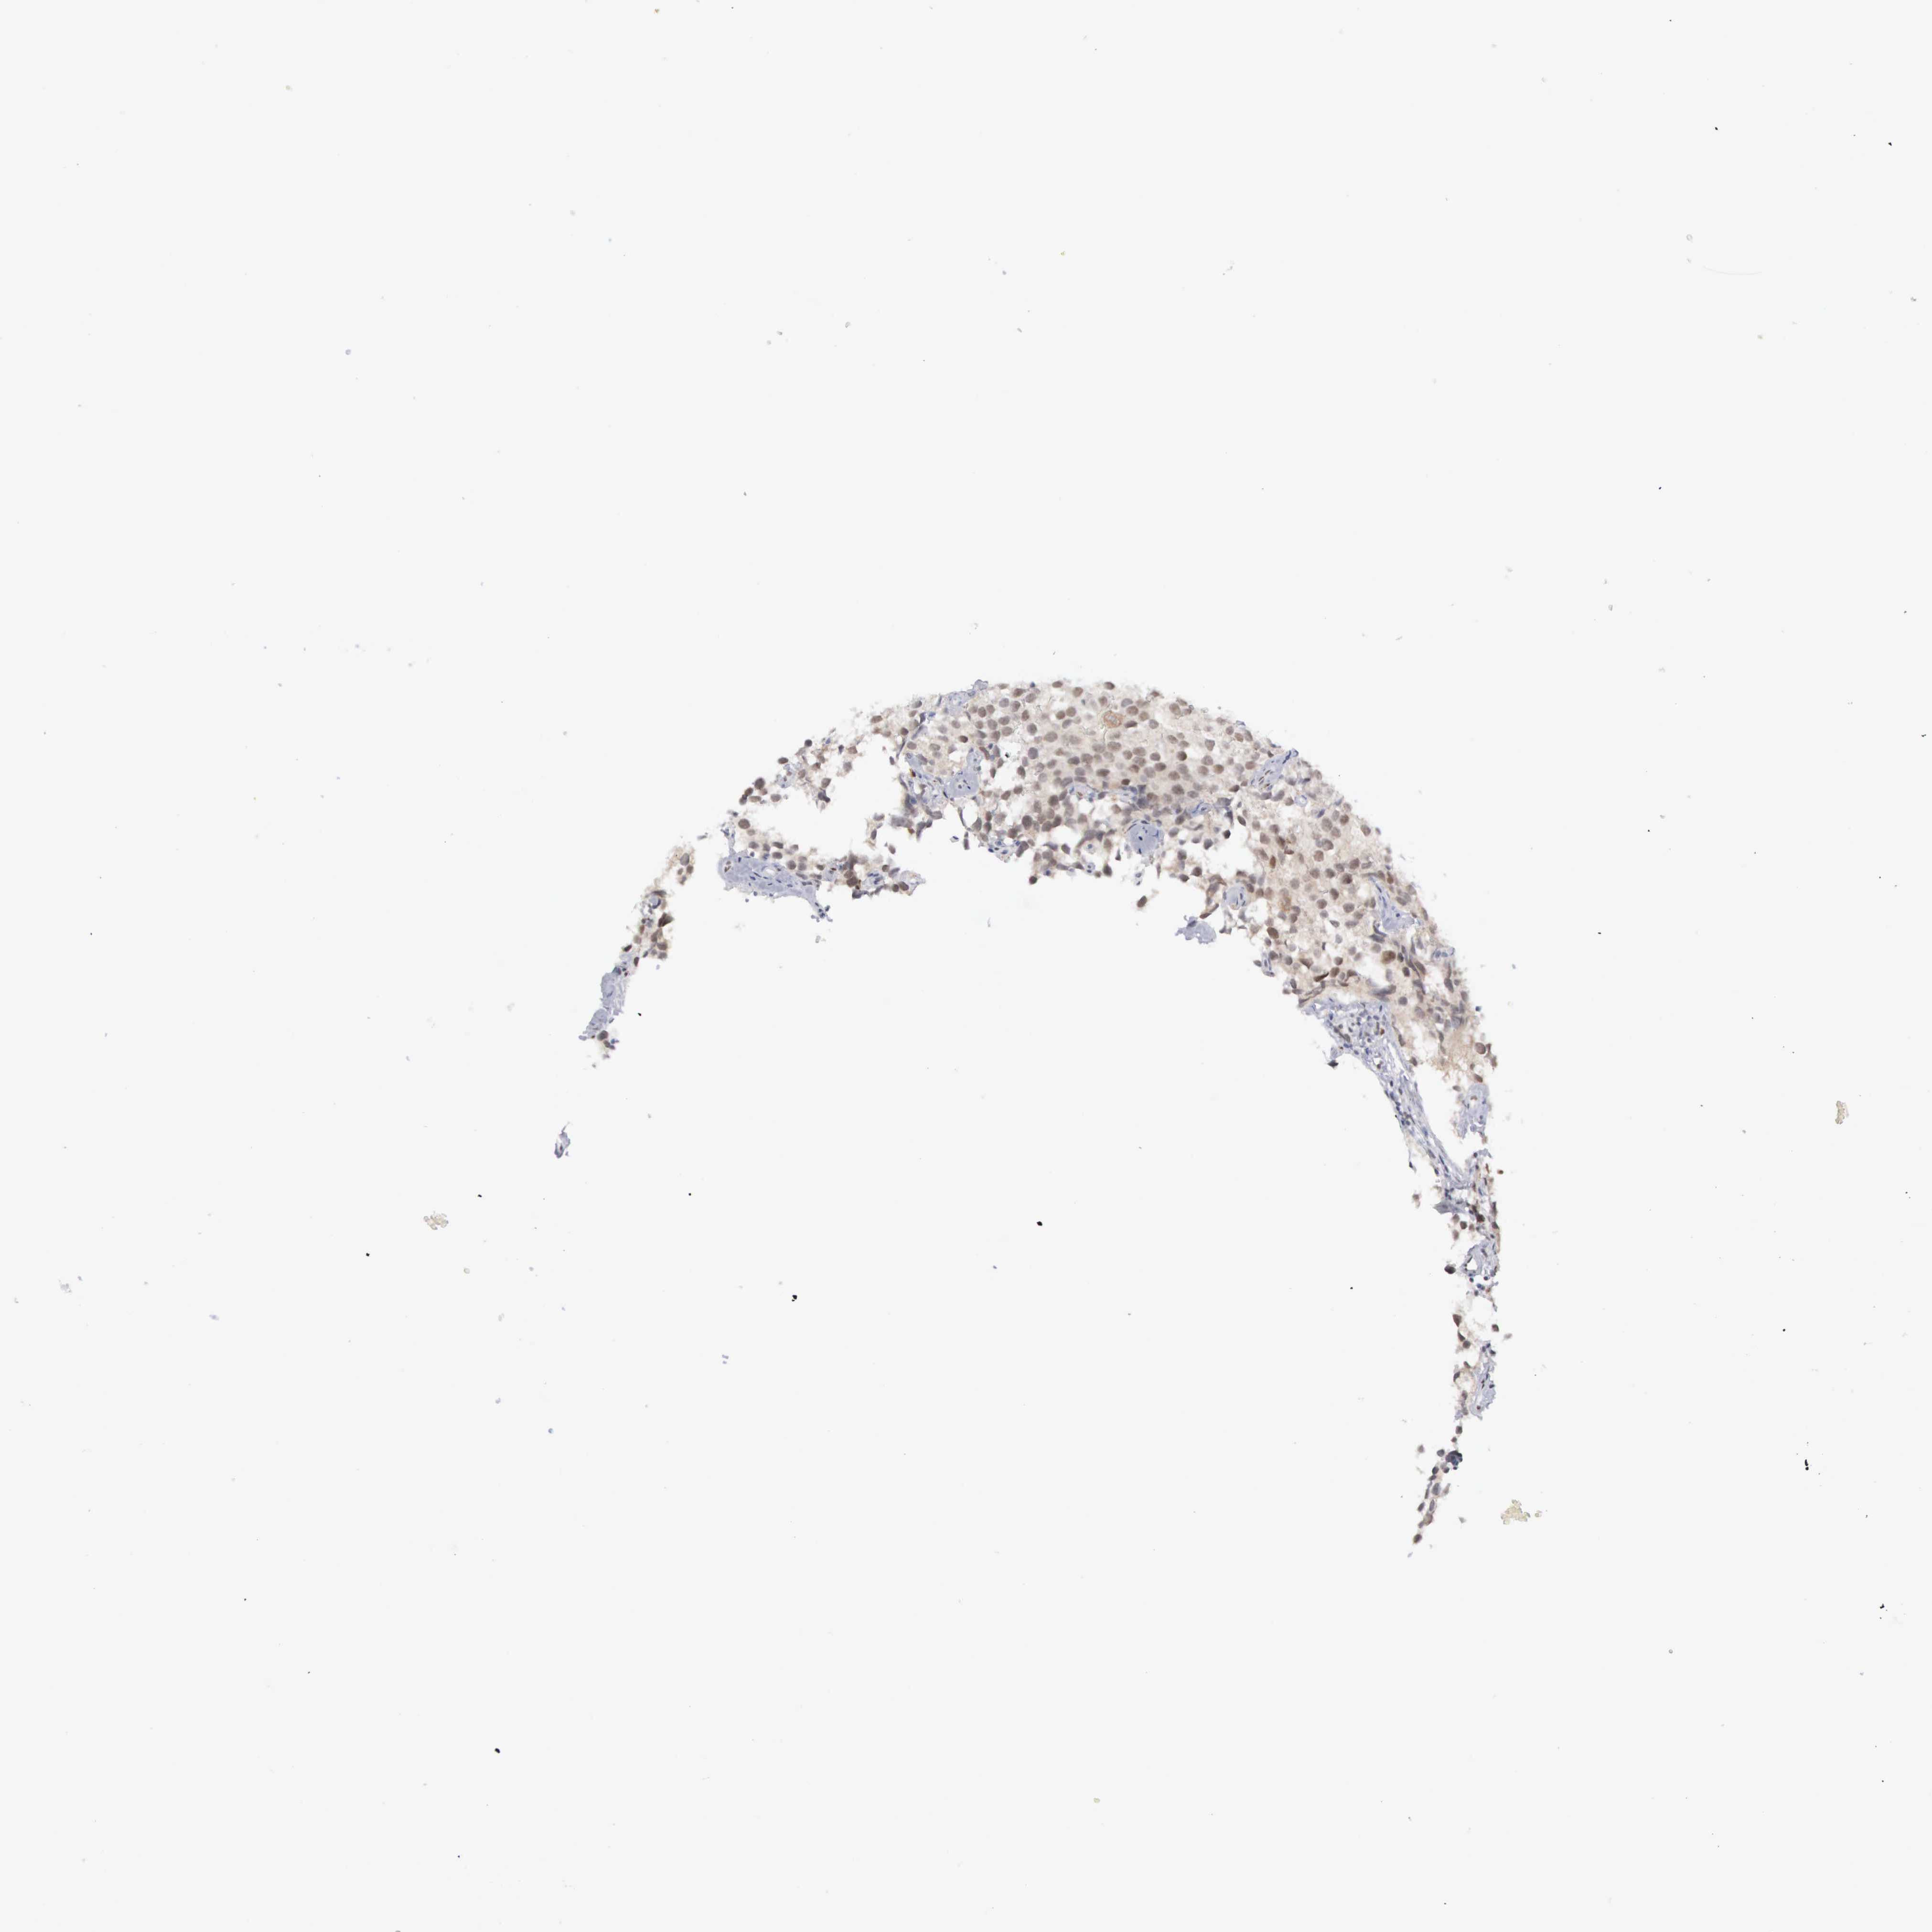

TESTIS CANCER - Protein expressioni

A mouse-over function shows sample information and annotation data. Click on an image to view it in a full screen mode. Samples can be filtered based on level of antibody staining by selecting one or several of the following categories: high, medium, low and not detected. The assay and annotation is described here.

Note that samples used for immunohistochemistry by the Human Protein Atlas do not correspond to samples in the TCGA dataset.

Antibody stainingi

Antibody staining in the annotated cell types in the current human tissue is reported as not detected, low, medium, or high, based on conventional immunohistochemistry profiling in selected tissues. This score is based on the combination of the staining intensity and fraction of stained cells.

Each image is clickable and will lead to virtual microscopy that enables deeper exploration of all samples and also displays staining intensity scores, fraction scores and subcellular localization as well as patient and tissue information for each sample.

Antibody HPA000701

Antibody CAB004495

Staining

High

Medium

Low

Not detected

Intensity

Strong

Moderate

Weak

Negative

Quantity

>75%

75%-25%

<25%

None

Location

Nuclear

Cytoplasmic/membranous

Cytoplasmic/membranous,nuclear

Seminoma, NOS

Carcinoma, Embryonal, NOS